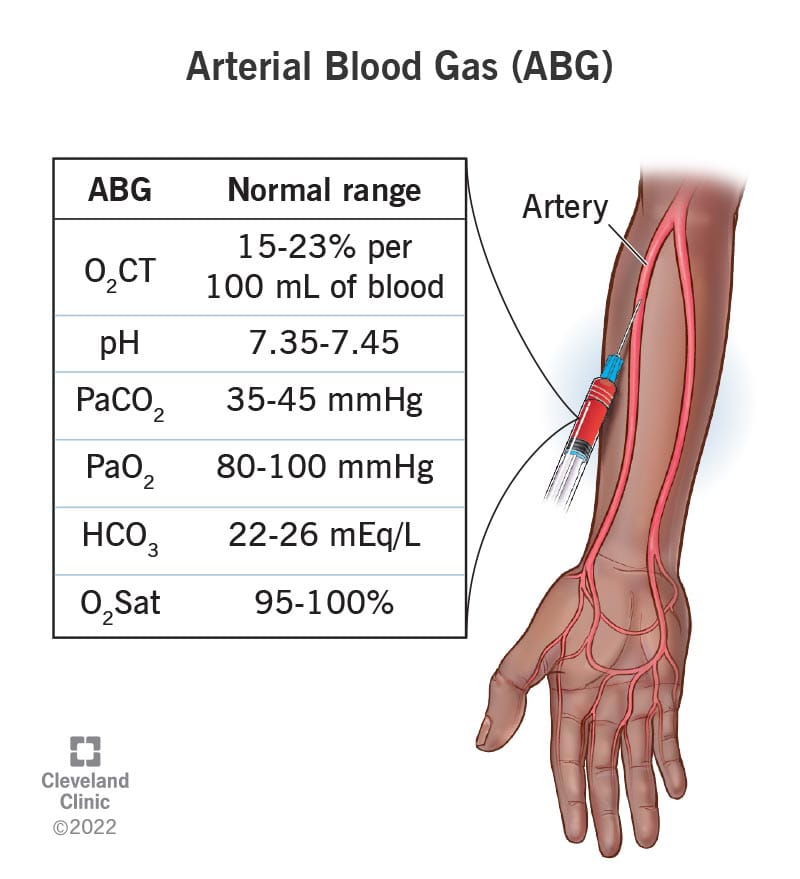

- આ ટેસ્ટ કરતા પહેલા એલેન ટેસ્ટ કરવામાં આવે છે જે હેન્ડમાં બ્લડ સપ્લાય કરતી આર્ટરીની (રેડીયલ અને અલ્નાર આર્ટરી) પેટેન્સી ચેક કરવા માટે વપરાય છે. Normal value of ABGs (નોર્મલ વેલ્યુ ઓફ ABGs)

partial pressure of oxygen – Pao2

• 75 – 100 mmHg

partial pressure of carbon dioxide – Paco2

• 35 – 45 mmHg

PH : 7.35 – 7.45

Bicarbonate – Hco3-

• 22 – 26 mEq/L

Oxygen content – O2CT

• 15 – 23% per 100 ml of blood

Oxygen saturation

• 95 – 100%

- એબ્નોર્મલ ABGs વેલ્યુ એ રેસપાયરેટરી અને મેટાબોલિક ડીસઓર્ડર સૂચવે છે.